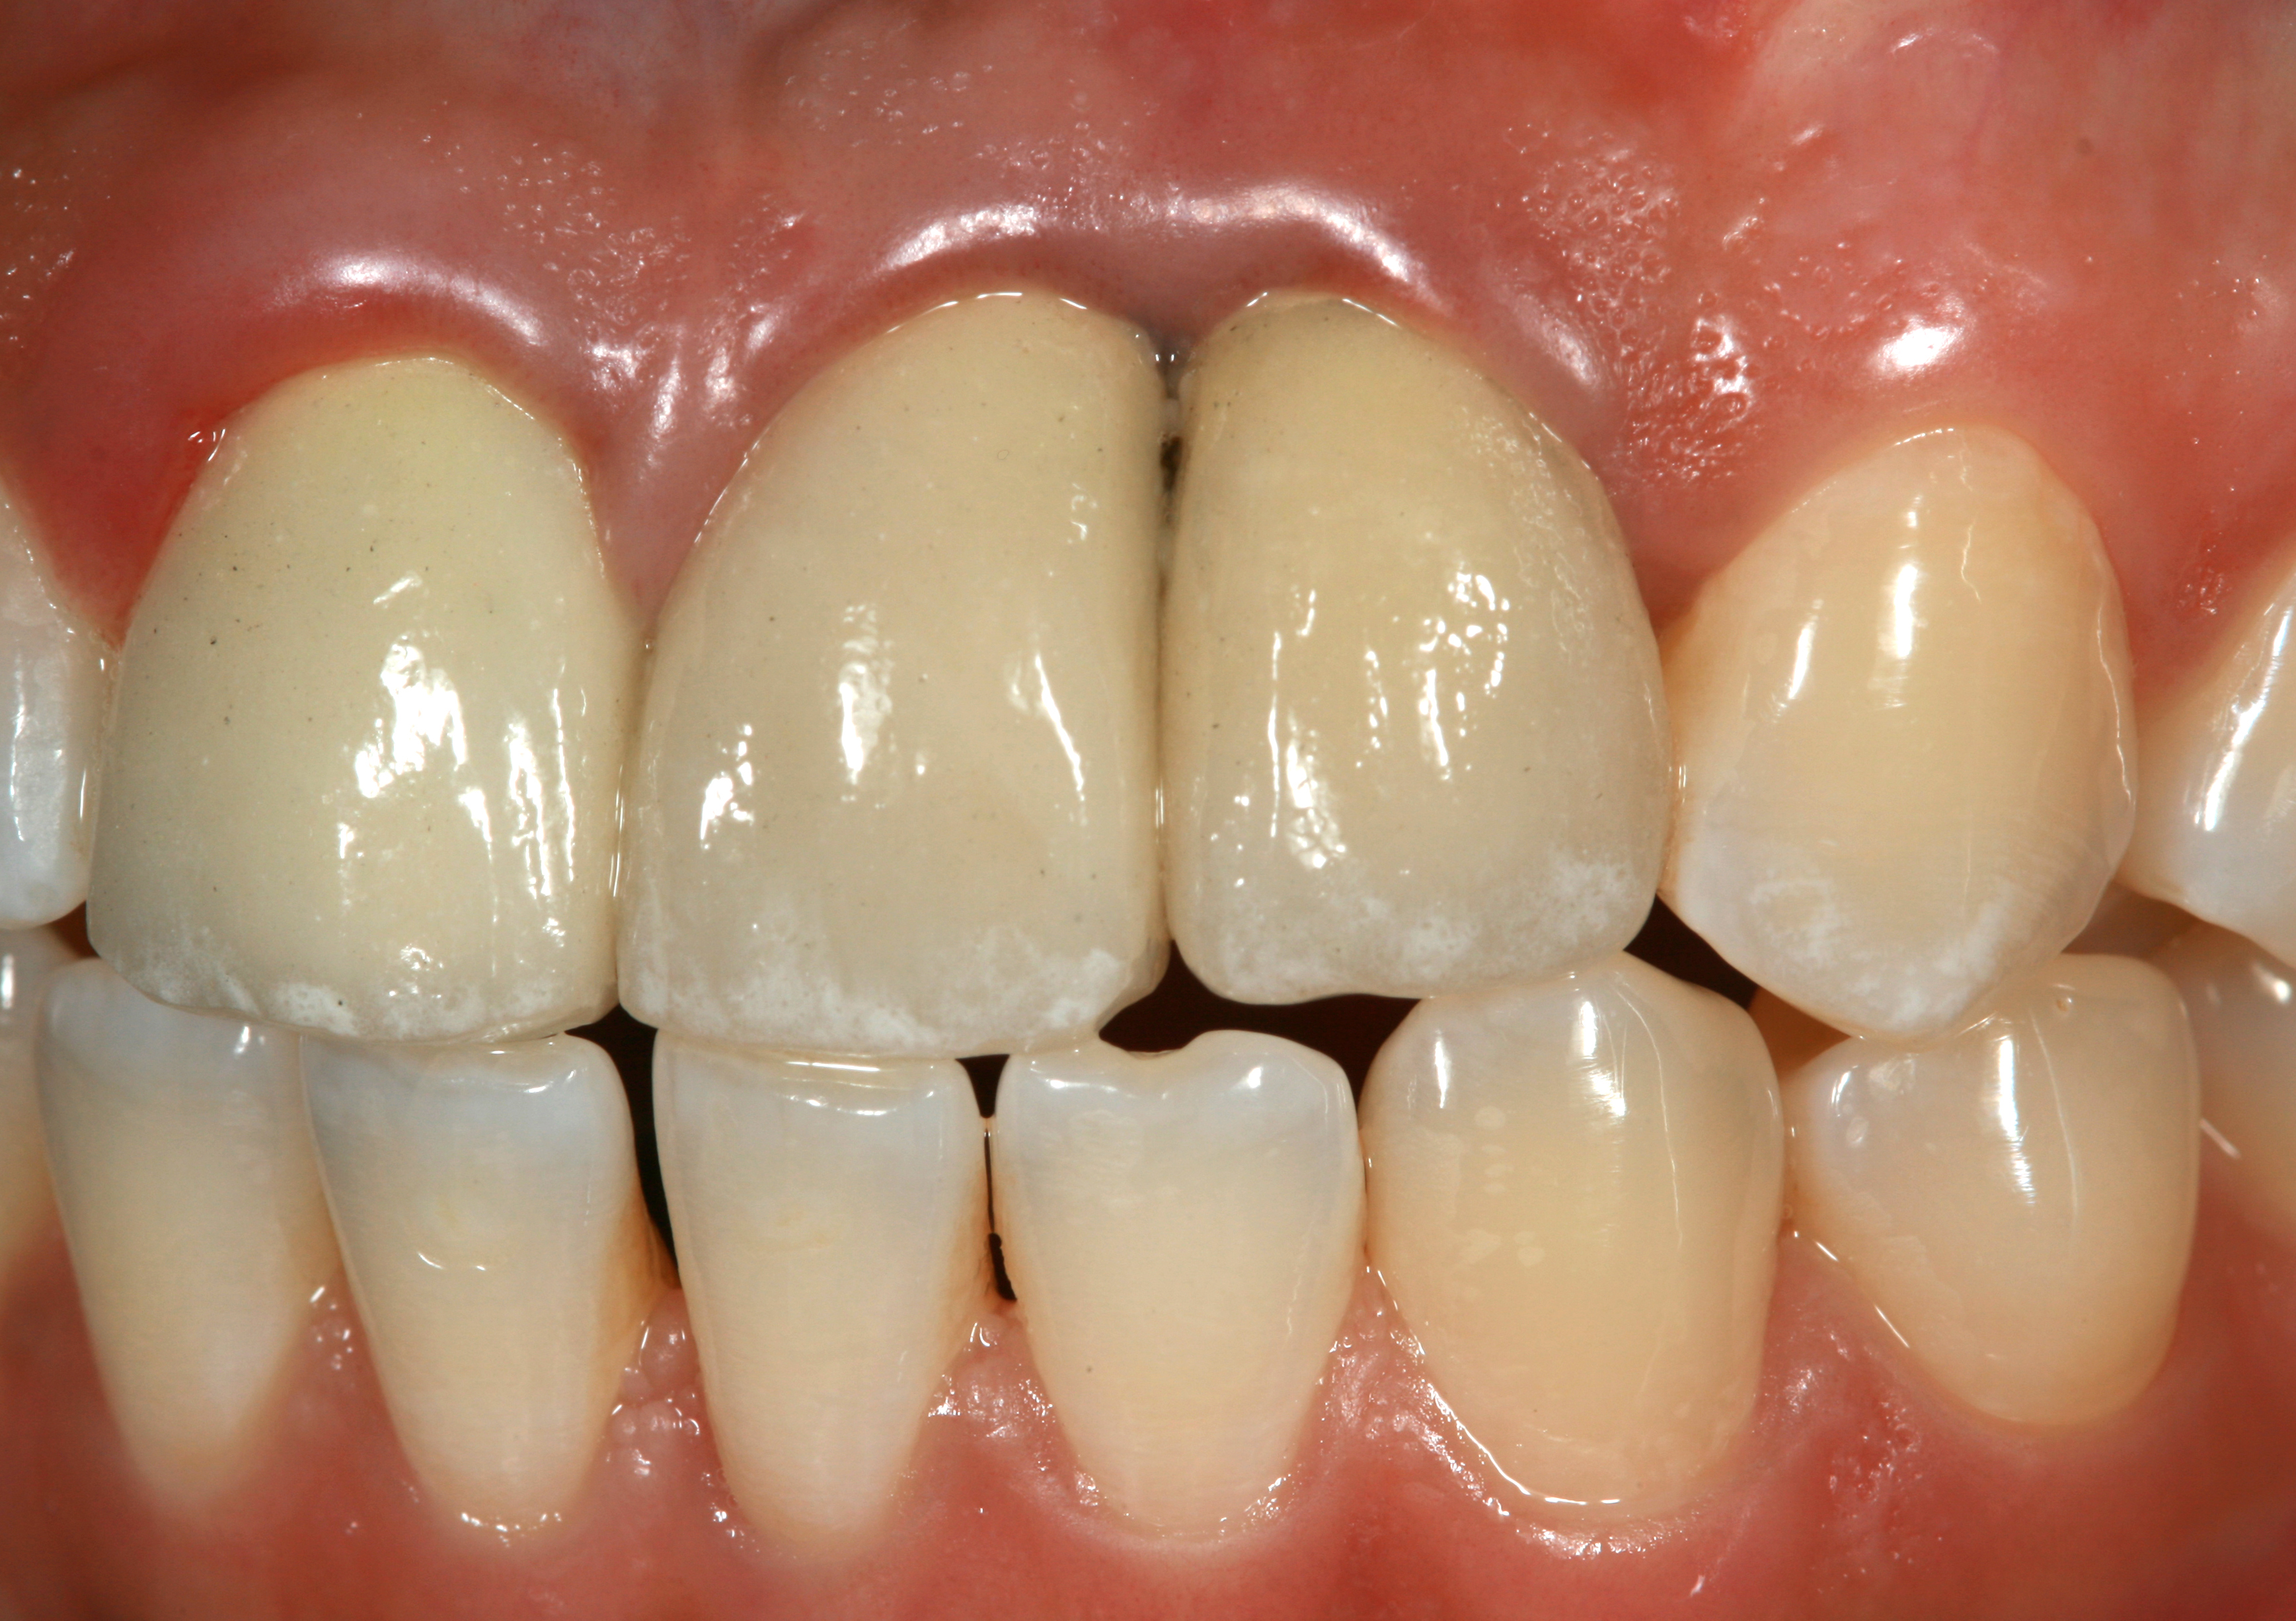

Problem: The implant is placed too facial with significant recession on the midfacial aspect of the abutment and/or crown; the implant is healthy and the patient has a high smile line with an intermediate to thick periodontal phenotype (Figure 1 and Figure 2).17-19

Fig 1. Midfacial recession can affect the esthetics of a smile and lead to an unsatisfactory outcome.

Fig 2. The cause for midfacial recession is excessive labial implant placement. Secondary to poor placement is overcontouring of the implant abutment.

Fig 3. A patient presented with a high smile line and midfacial recession of the maxillary right lateral incisor as evidenced by the increased tooth length compared with the contralateral lateral incisor.

Fig 4. Intraoral view of tooth No. 7 with the gingival zenith more apical than the adjacent central incisor and canine tooth.